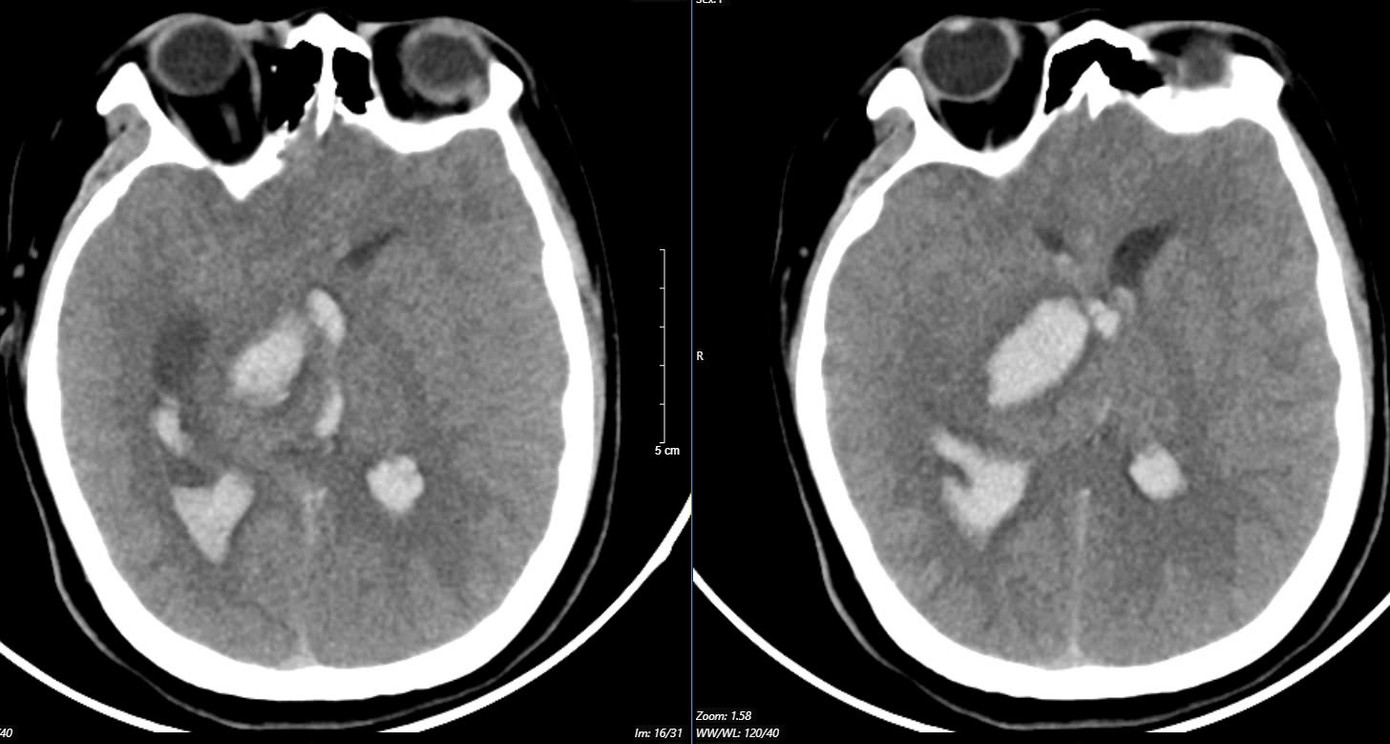

Hình ảnh chụp MSCT mạch não: Chảy máu não thuỳ đỉnh phải, chảy máu não thất do vỡ AVM ( điểm Spetzler Martin 2 điểm) bệnh nhân nữ, 29 tuổi. Ảnh: Bệnh viện Bạch Mai

Trường hợp thứ ba: Nữ bệnh nhân 29 tuổi, tiền sử khoẻ mạnh. Bệnh nhân đến viện vì đột ngột đau đầu, tê tay, nôn nhiều vật vã. Tại bệnh viện tỉnh, bệnh nhân được chẩn đoán chảy máu não, các bác sĩ đã đặt ống nội khí quản thở máy rồi chuyển tuyến lên Trung tâm Đột quỵ, Bệnh viện Bach Mai trong tình trạng ý thức hôn mê, Glasgow 6 điểm, thở máy, đồng tử bên phải giãn 4mm, tụt huyết áp, duy trì vận mạch. Chụp MSCT mạch não: Chảy máu não thuỳ đỉnh phải, chảy máu não thất do vỡ AVM ( điểm Spetzler Martin 2 điểm). Bệnh nhân đã được phẫu thuật lấy máu tụ và khối dị dạng. Tuy được điều trị tích cực nhưng di chứng để lại vô cùng nặng nề. Sau một tháng điều trị, bệnh nhân chưa nhận thức được, liệt hoàn toàn nửa người trái…